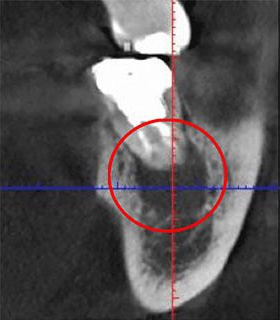

下はCTとレントゲンで撮影したものを比較した画像です。

赤い丸で囲ったのが問題のある部分ですが、レントゲン写真では問題のある部分が写し出せていません。

問題のある場所が分からなければ、適切な治療はできません。どこに問題があるかを正しく把握することが根管治療では大切になってきます。